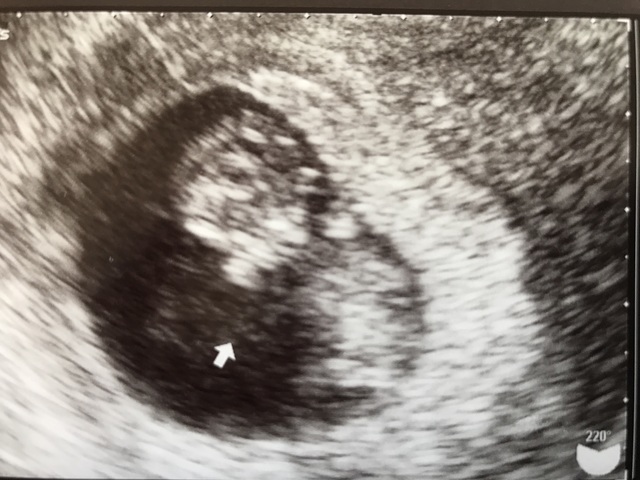

我が家にとっては初めての赤ちゃん。 2年以上の不妊治療を経て、顕微授精でようやく授かりました。採卵後すぐの移植で授かったため卵巣が10cm近くまで腫れてしまい、嬉しさももちろんあるものの不安の方が強かったです。

不安の中映し出された赤ちゃんの姿は雪だるまのようにまあるくて顔の横に手を添えていてとてもかわいらしく愛おしく思いました。

今は20週を超えてここまで育ってくれたことに感謝です。まだ性別はわかりませんが、健康で元気に生まれてきてくれることを心から願っています。